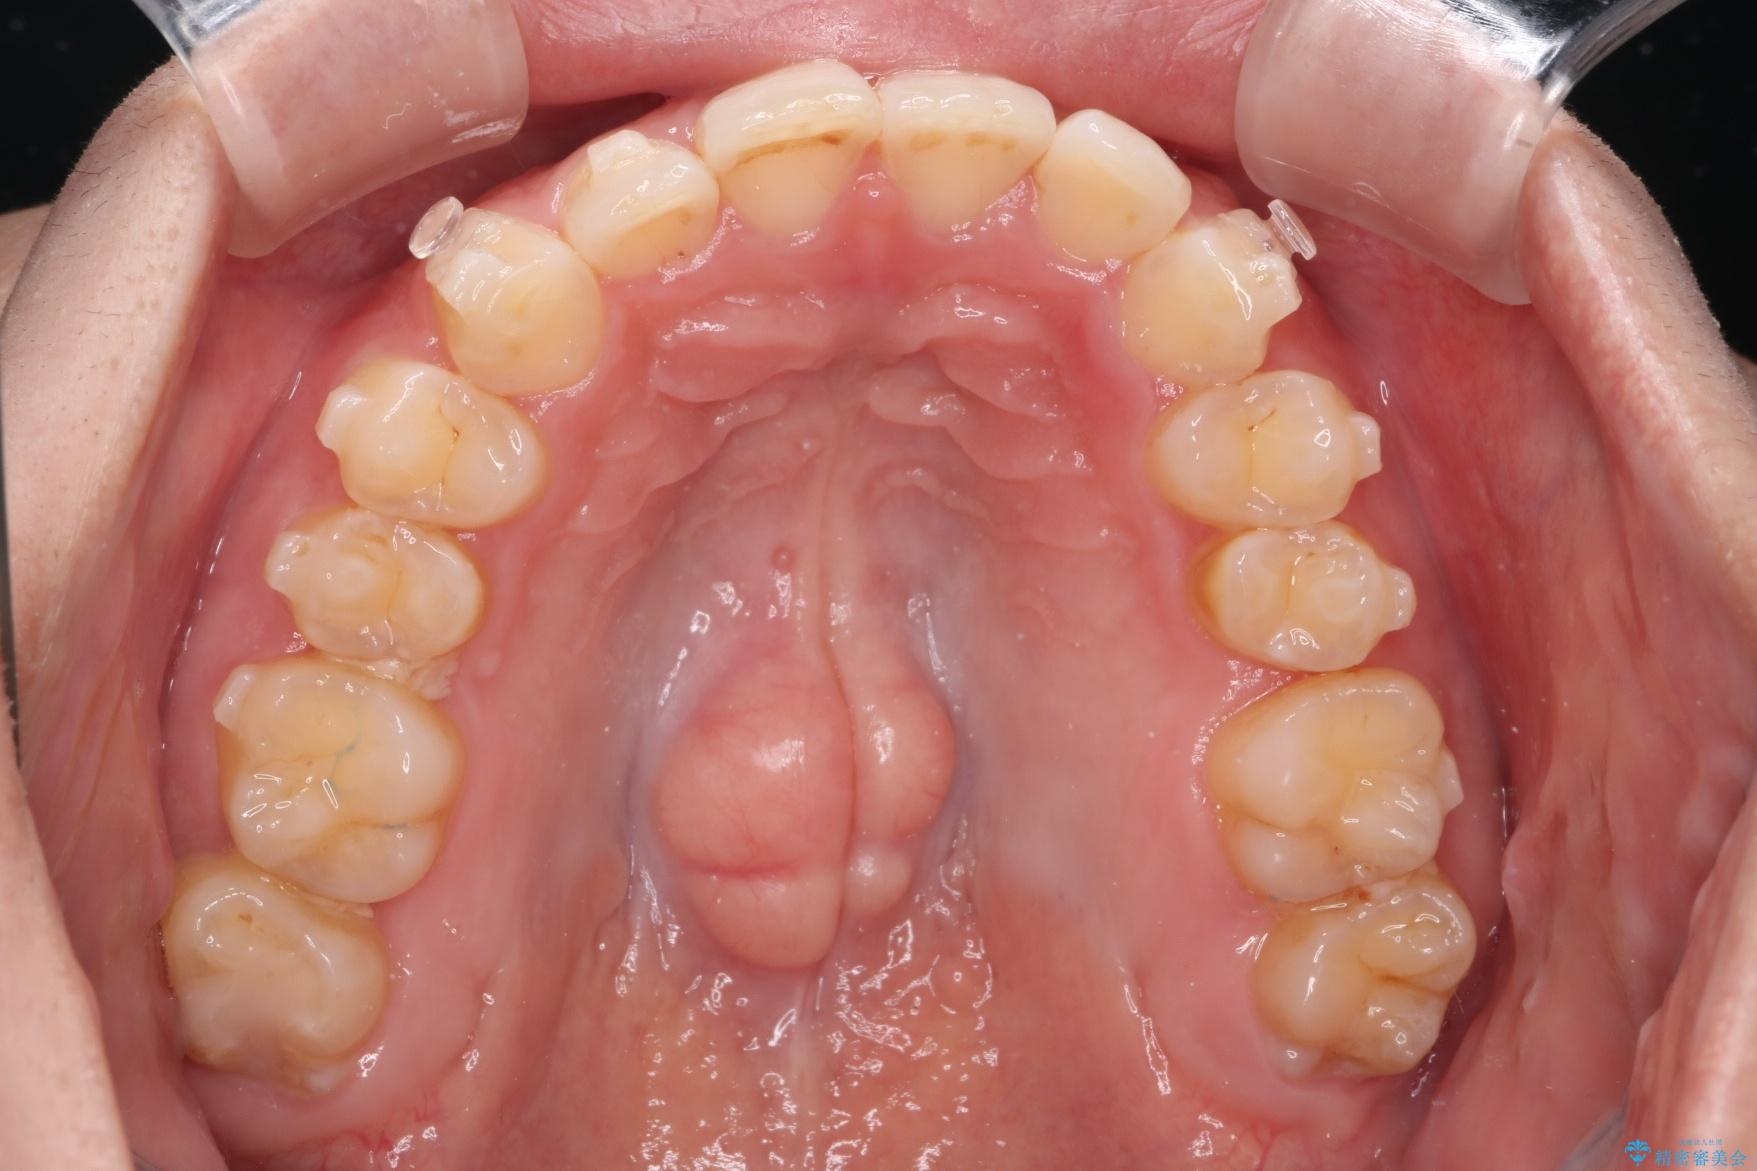

- 下の歯のがたつきを主訴に来院されました。

下の歯のがたつきと右の奥歯の噛みあわせ改善するために治療計画を立てることにしました。

右側臼歯部の咬合改善のために、臼歯部のみ部分的なワイヤー矯正を行い、咬合改善がみられてからインビザラインにて全体的な矯正を行なっていく治療計画を立てました。